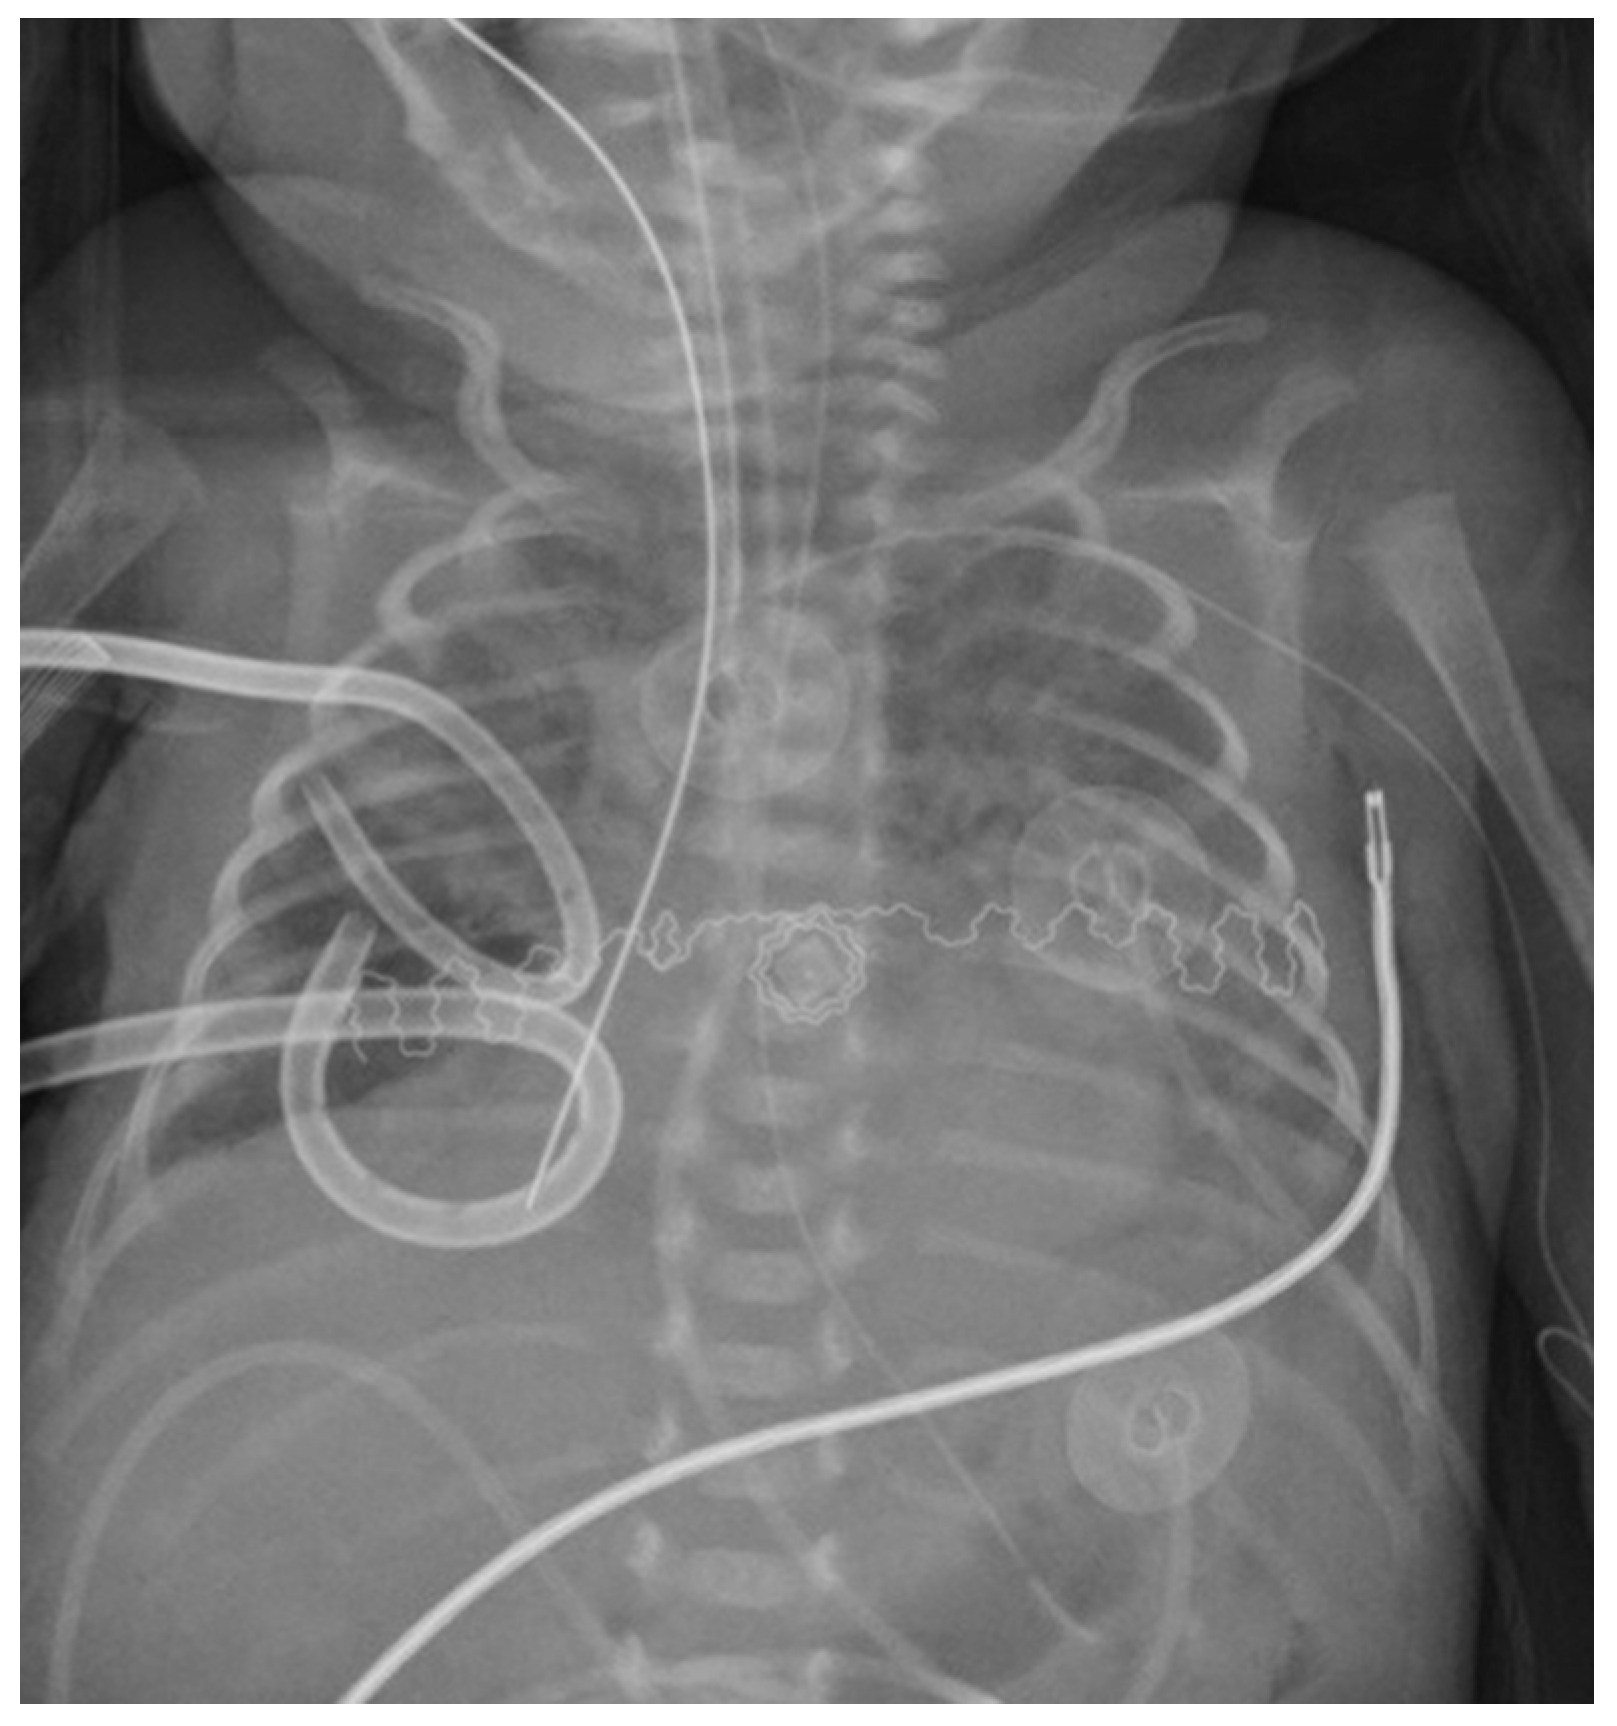

| Present study | 27 | 600 | PTX | Right | Chest drainage and postural therapy | Yes | Fogarty’s catheter 3 FR, inflated 0.2 mL | Direct laryngoscopy | Inflated 1 h/deflated 2 h | 72 h |